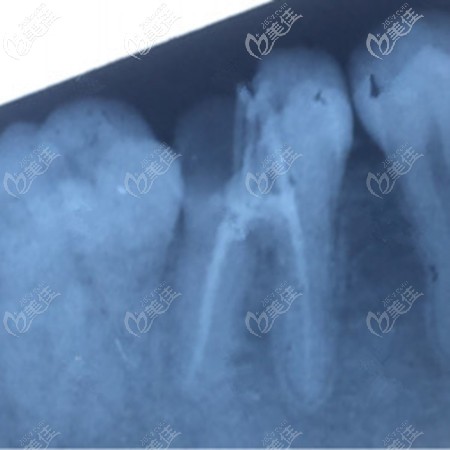

術(shù)后照片:

到院后,醫(yī)生就先給我拍片,看看牙齒的基本情況。牙齒的狀態(tài)還是不錯(cuò)的,牙神經(jīng)沒有受損,就是牙齒缺了一個(gè)口子,也不用做根管治療,只用補(bǔ)牙就可以了!